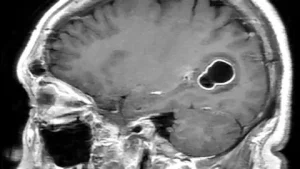

1. MR (Manyetik Rezonans) Görüntüleme

Beyin kistlerinin tespitinde en etkili yöntemlerden biri MR’dır. Manyetik rezonans görüntüleme, beyin dokusunu ayrıntılı bir şekilde görüntüleyerek kistlerin yerini ve büyüklüğünü belirler.